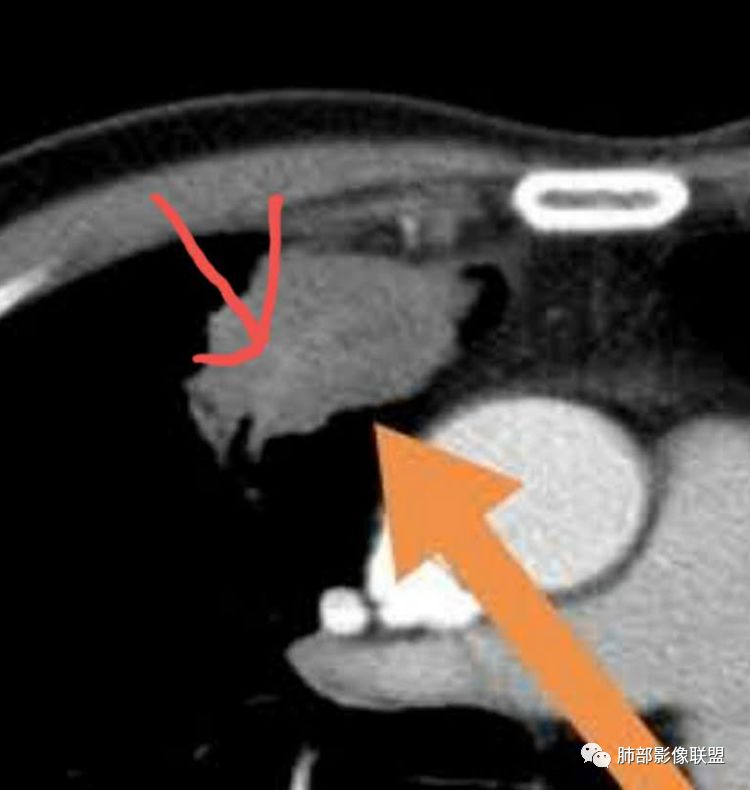

冥冥之中:体循环供血,仅此一条,加上老年,孤立肿块,咳血,基本上锁定恶性了。

郑氏刀刀:截断支气管伴行的血管,增粗,但是无明显破坏浸润。

增粗的是静脉。

回流增加?炎性刺激的静脉扩张?

胸膜下脂肪间隙增宽,怀疑是静脉被牵拉扩张的。

尘缘:@李双喜,阳朔县医影像科?内乳动脉增粗有意义,但不能直接鉴别良恶性,可以提示这个病灶时间比较久了,慢性炎性肉芽肿和肿瘤都可以增粗。Coke with ice:

南边:内乳的血管,没看到与病灶的关系啊。

郑氏刀刀:动脉没有增粗,静脉增粗了,静脉平滑肌薄,容易扩张。这样的边缘炎性一定有

尘缘:栽赃不明显,血管应该进入了,但是显示不够确切。